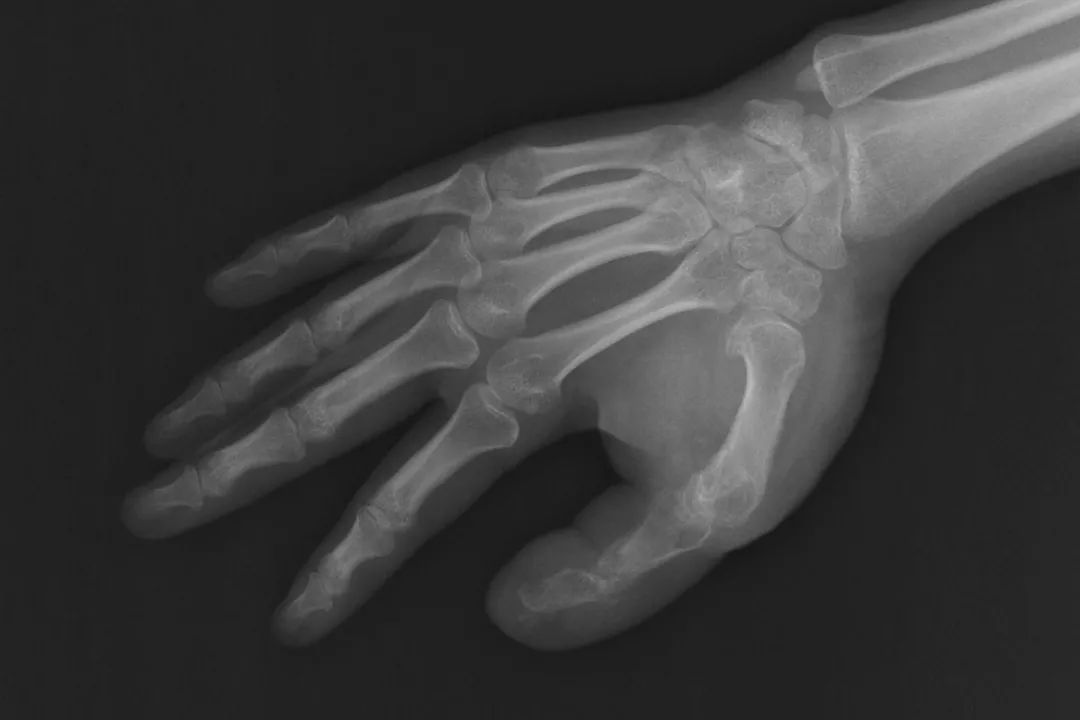

(术前通过X线片测量并设计截骨方案)

(截骨后,拇指指骨接近正常大小)

一期手术前,医生通过X线片测量手术切口并设计截骨方案,截骨后,拇指指骨已经接近正常大小。术后病理证实,何女士的巨指症属于典型的神经脂肪瘤病。通过制定个性化手术方案期并进行分期的手指外形的修复,目前巨大的手指外观得到了很好的改善。